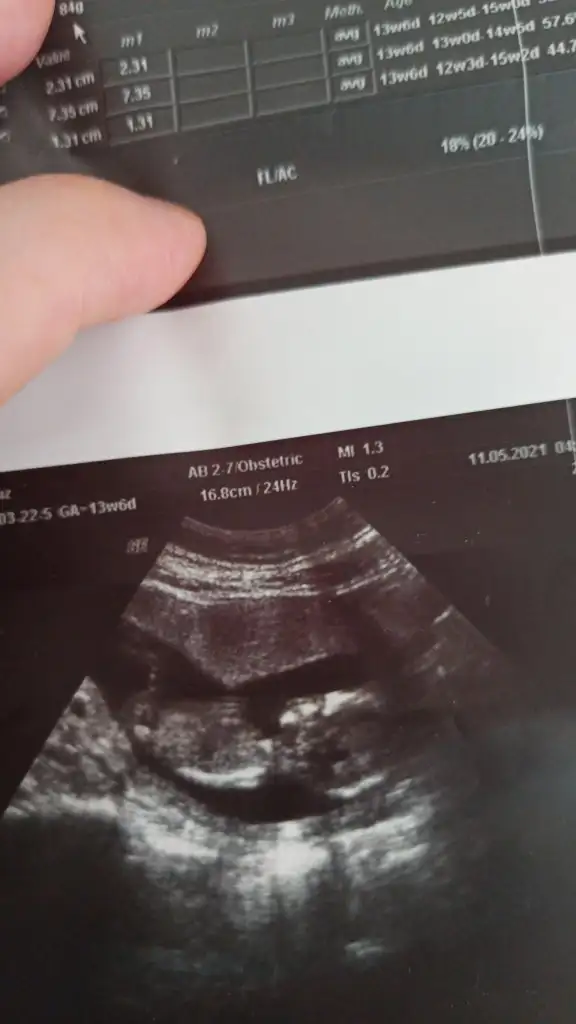

Kızlar cinsiyetimiz belli oldu doktor yüksek ihtimalle kız dedi . Çin takvimi Rus takvimi ramzi teorisi maya takvimi japon takvimi hep erkek gösteriyordu hiç biri tutmadı. Bir tek nub teorisi tuttu bebeğin çıkıntısı düzdü yukarı doğru değildi ☺️ Cinsiyet değişir mi bilmiyorum tabi çünkü daha 13+6 yiz🥰

Canım 6 7 haftalıkken karından sol taraftaydi şimdi 12+3 ve 13+6 yi atacağım 12+3 deki çıkıntı düz bakıyor nub teorisi diyoruz buna ordan kız olduğunu anlamıştım